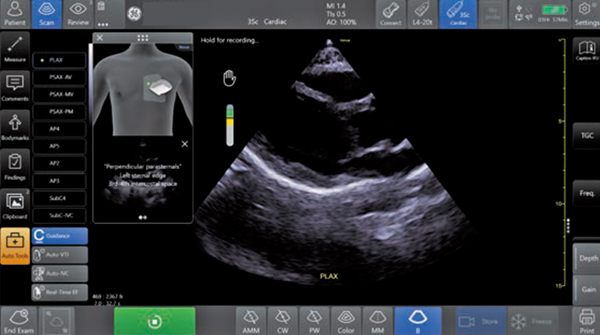

今回,新たにAIを用いて開発されたCaption Guidanceは,心エコー検査において,AIがプローブ位置を含む撮像の状態を認識し,リアルタイムに操作者にガイダンスを行うことで,心エコーに慣れていない医療従事者でも高いクオリティの画像が安定して得られるよう撮像自体をサポートする機能である。そのため,医療従事者に対して検査,手技のワークフロー向上や初学者への教育をアシストするだけでなく,患者に対して高いクオリティの安定した心エコー検査を提供することを目的としたサポート機能であることが,従来のAI技術とは異なる点である。

Caption Guidanceでは,心エコー検査時に,操作者に対してリアルタイムでプローブ走査をガイド表示し,プローブを当てる位置,角度,マークの方向など,正確で高いクオリティの画像が得られるようにサポートする。これにより,複雑な心エコー検査をより簡便かつ正確に行うことが期待できる。また,最適なスキャン画像が得られているかの判断をアシストするインジケータ機能も備えており,スキャン画像が一定レベル以上のクオリティと認識された際に,操作者がプローブの位置を一定時間維持することで,自動的に画像を保存することも可能である(図3)。

従来型の心臓用セクタープローブに加え,ワイヤレスプローブでも活用できるため,特に心エコーの初学者への教育を行う大学・基幹病院のトレーニングセンターでの活用や,救急患者,集中治療室,周術期の入院患者に対する心エコー検査のアクセス拡大や,よりスムーズな心エコー検査の補助など,さまざまな用途での活用が期待される。

図3 Caption Guidance